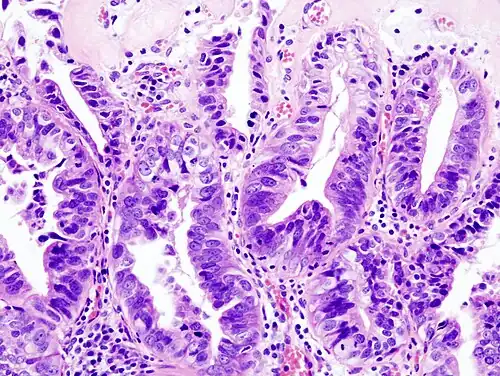

-

Gallbladder adenocarcinoma lymphatic invasion histopathology -

Incidentally discovered gallbladder cancer (adenocarcinoma) following a cholecystectomy. -

Gallbladder adenocarcinoma histopathology

Most tumors are adenocarcinomas, with a small percent being squamous cell carcinomas.